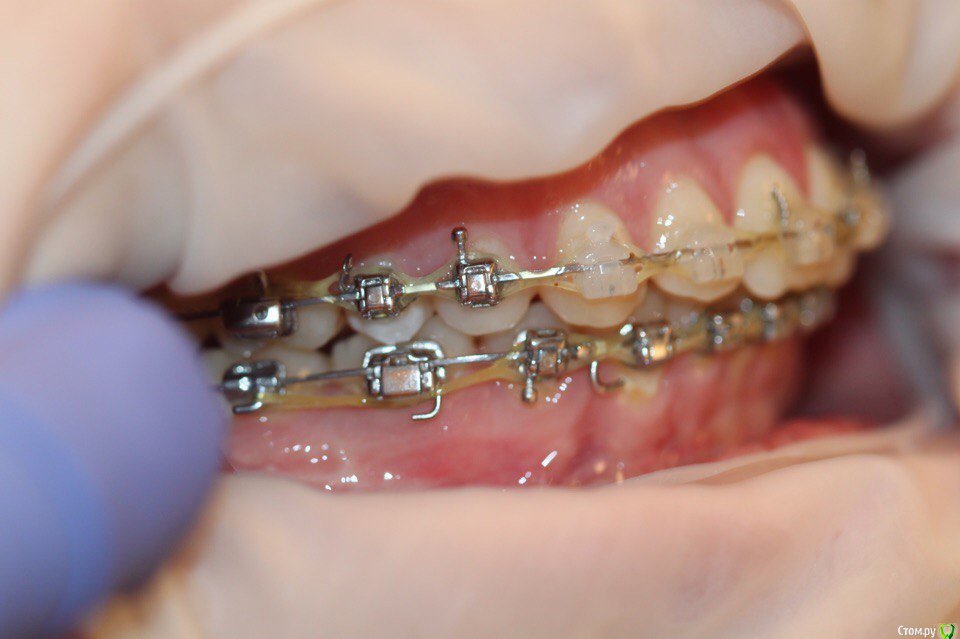

annurka Опубликовано 12 сентября, 2017 Поделиться Опубликовано 12 сентября, 2017 (изменено) здравствуйте! 24 года, дисфункция ВНЧС, дистальный прикус (1,4см), ортодонтическое лечение начато с ношения каппы для разгрузки сустава (привыкла подтягивать НЧ к верхней) в 2012 году. проведено лечение: удаление всех 8к (непрорезавшиеся), расширение ВЧ (аппарат дерихсвайлера), выравнивание зубных рядов, сепарация нижних резцов (резцы были наклонены), места не хватило - удаление 2 нижних 4к, выравнивание кривой шпее, двухчелюстная остеотомия; выравнивание окклюзионных контактов (резиновые тяги) проблема: между верхними и нижними резцами расстояние 5мм к трг (внизу фото) есть расшифровка.все идет к снятию брекетов, и с эстетической точки зрения меня все устраивает. но не до конца устраивает в функциональном плане (я не могу пропихнуть палец между зубными рядами, как раньше, но все также подтягиваю челюсть кпереди когда ем, говорю)стараюсь контролировать это, но даже улыбнуться не могу не подтянув - иначе у меня некрасиво вырисовывается подбородок, неправильно произношу звуки при разговоре.сразу после остеотомии состыковка резцов была ок - нижние зубы были за верхними, но мы с ортодонтом занялись состыковкой и других зубов (которые тогда не соприкасались), и когда добились контактов жующих сторон, разошлись резцы.UPD: и еще есть черные треугольники на НЧ - с ними тоже очень хочется разобраться лечащий ортодонт говорит, что это в целом норма, с учетом моего случая. и возможно это так, но я очень хочу послушать еще мнений, возможно стоит удалить 2 зуба наверху, чтобы верхняя челюсть подошла по размер нижней? [боюсь что простой сепарации может не хватить и как в случае с нижними резцами придется и сепарацию делать, и удалять зубы.] может быть еще есть другой способ добиться нормального прикуса, без "нюансов"?изначально я пошла на все это лечение, чтобы остановить разрушение сустава (однажды проснулась и не смогла рот даже открыть, еще до лечения), полагала, что брекеты и члх исправят если не ситуацию, то причину, но я все еще двигаю НЧ вперед к ВЧ. с остеотомии прошел почти год (поэтому на изменение картины эластиками я уже не надеюсь), брекеты ношу почти 4 года. заранее всем спасибо за отклик! Изменено 12 сентября, 2017 пользователем annurka 1 Ссылка на комментарий

annurka Опубликовано 13 сентября, 2017 Автор Поделиться Опубликовано 13 сентября, 2017 (изменено) А До лечения есть ТРГ посмотреть? И фото какие-нибудь?есть трг сверху - сразу после остеотомии, снизу - через полгода после (когда резцы отошли друг от друга на 5мм) до лечения вообще точно делал ортодонт (снимки, слепки, фото), если в клинике это сохранили, я смогу сфотографировать. далее фото в процессе лечения - 4ки нижние еще не удалены, один хирург был готов так оперировать, другой сказал, что наклон нижних резцов неправильный и нужно как и было запланировано удалить 4ки, сепарации недостаточно.челюсть расслаблена как есть: НЧ подвинута к ВЧ для наглядности: есть фото слепков того периода, но форум ругается на слишком большой размер. если нужно - уменьшу залью) Изменено 13 сентября, 2017 пользователем annurka 1 Ссылка на комментарий

annurka Опубликовано 13 сентября, 2017 Автор Поделиться Опубликовано 13 сентября, 2017 (изменено) вот трг до начала лечения, фото к сожалению нет, если только из жизни) расшифровка трг ДО (где выделено синей ручкой) и недавнее Конечно контакты не идеальны, но если удалить 4ки наверху нижняя треть лица будет иметь довольно вогнутый вид спасибо за комментарий! а если сделать сепарацию резцов, тогда получится избежать вогнутости профиля? С ДВНЧС у вас сейчас проблемы остались? Можно рассмотреть совместно с врачом аппараты для выдвижения нижней челюсти,если тяги не справляются не было до недавнего времени - сейчас иногда болит в области сустава слева (видимо потому что контакты справа уже есть, а слева в процессе, поэтому нагрузка на челюсть неравномерная ?). до операции (но после начала лечения брекетами) сустав не беспокоил, надеюсь это просто период реабилитации.насчет аппаратов по выдвижению НЧ - спасибо, передам ортодонту.с6нимки к сожалению выполнены в разных клиниках, но мне казалось что если судить по трг через полгода, то НЧ там же, где была закреплена титановыми пластинами сразу после остеотомии (но проблема с резцами тогда уже возникла)... или мне так только кажется и произошел рецидив? думаете ее можно еще двинуть вперед? Изменено 13 сентября, 2017 пользователем annurka Ссылка на комментарий